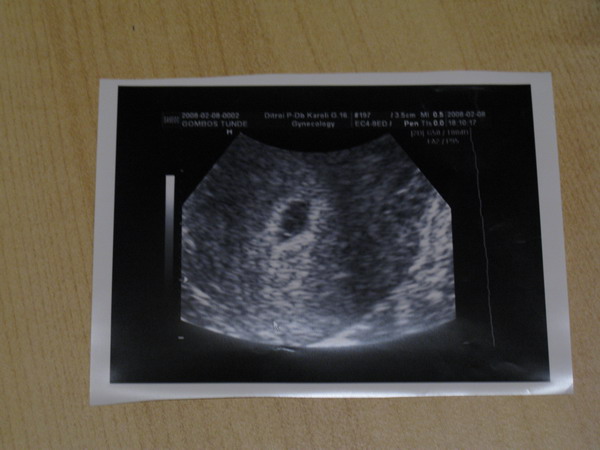

Megjöttem dokibától. Hát nagyon rendes, kedves meg alapos volt. Ilyennek kellene minden dokinak lenni. Jót választottam. :) Igaz, csak erre az UH-ra, de valszeg majd 4D-re is hozzá megyünk.

Naszóval. Van egy 7 mm-es petezsákom, benne egy szép szikhólyag (az a kerek kis vmi). :)

Íme: